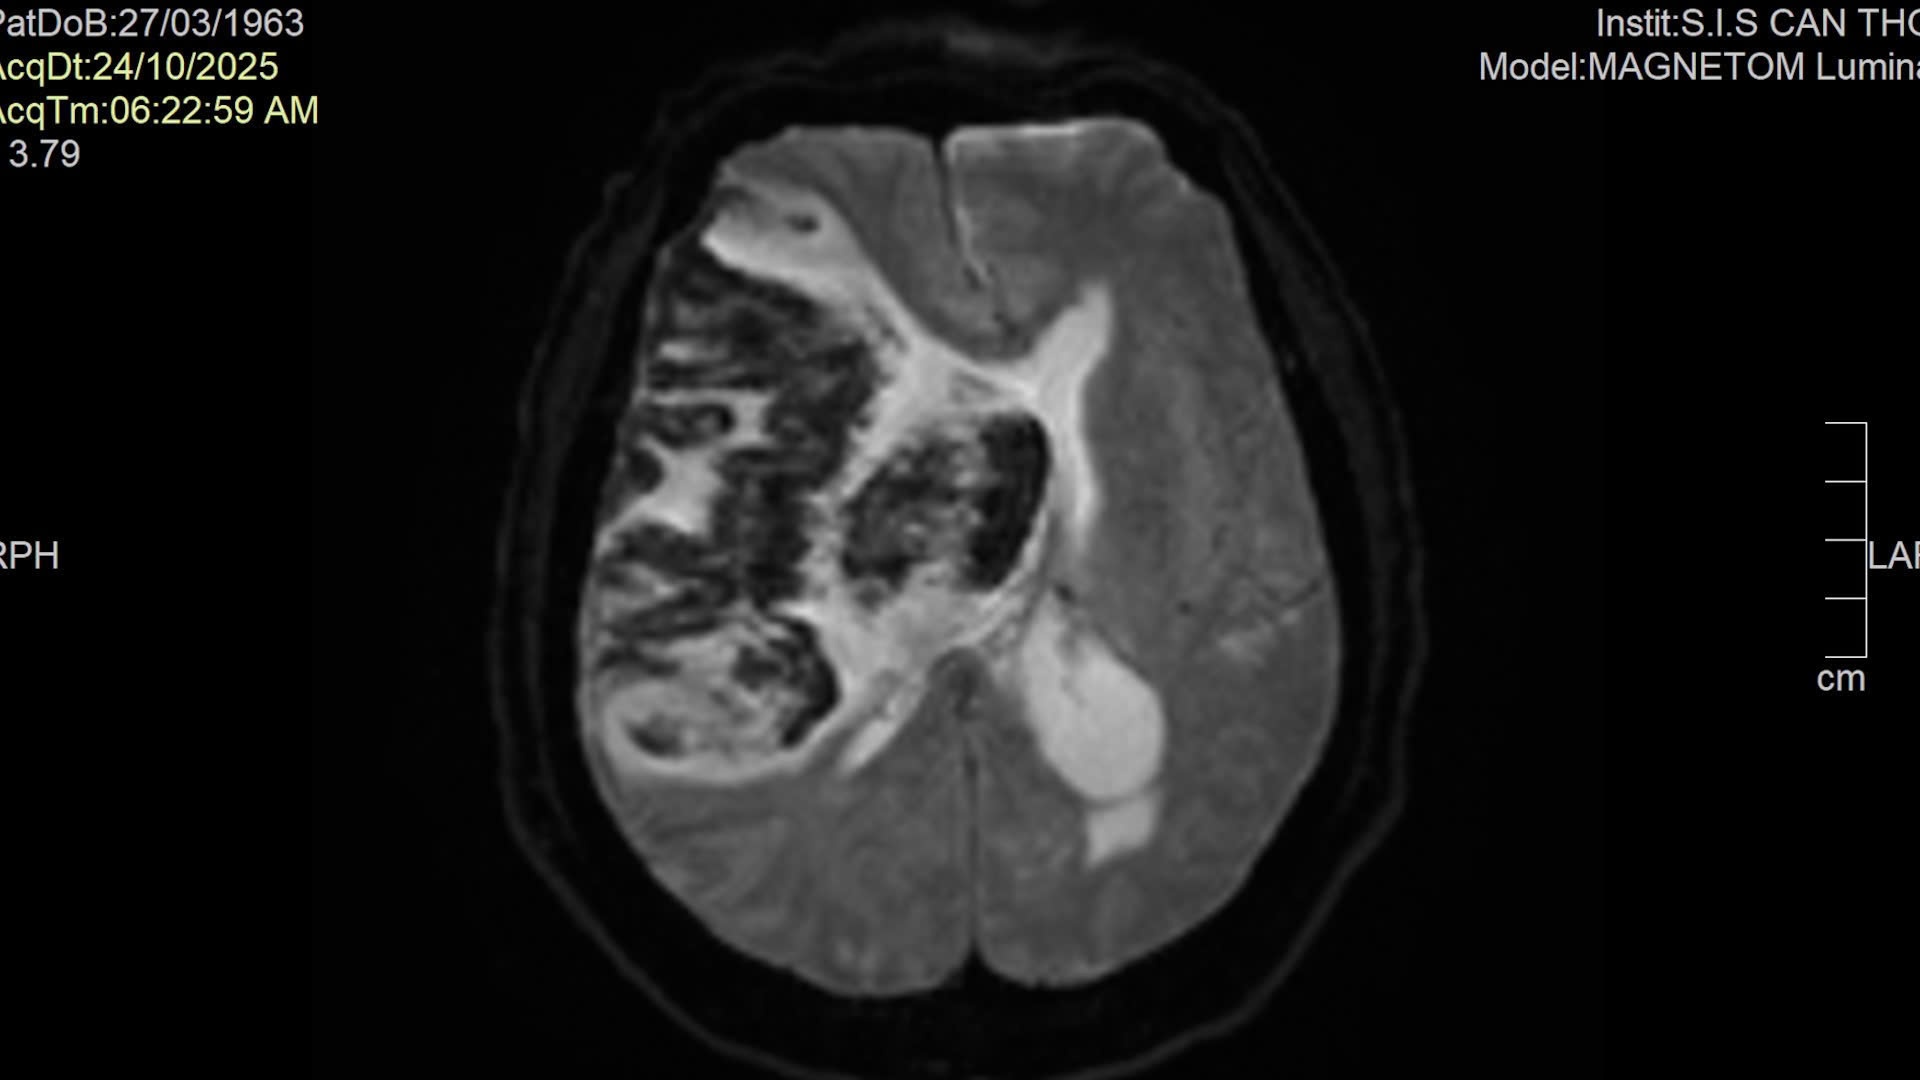

Bệnh nhân tên N.T.H, 62 tuổi (ngụ phường Khánh Hội, TP. Hồ Chí Minh), nhập viện trong tình trạng hôn mê sâu (GCS 4 - 5 điểm), phải thở máy. Kết quả chụp MRI não cho thấy nhồi máu não diện rộng vùng bán cầu phải chuyển dạng xuất huyết, phù não nặng, kèm nhiều bệnh nền phức tạp như tăng huyết áp, đái tháo đường, rối loạn mỡ máu, bệnh tim thiếu máu cục bộ.